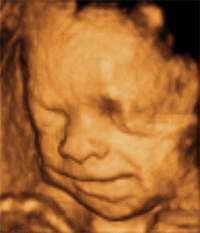

3rd Trimester Anomaly Scan

The NHS fetal screening program does not offer any routine scans after the 18-20 weeks anomaly scan meaning most women won’t have any additional baby’s checks before its birth. This scan aims to screen for birth defects with late manifestation (especially for anomalies of the brain, heart and the kidneys). This period is the best for clinical use of 3D/4D.